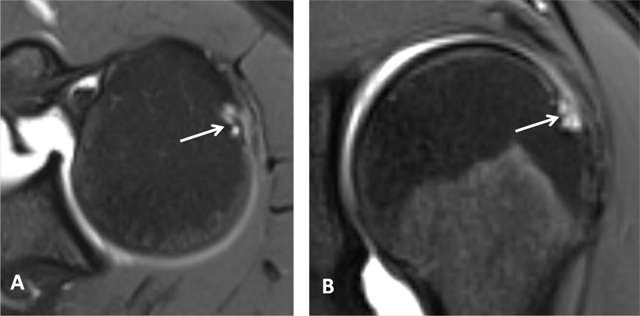

Figure 2

Normal red bone marrow in a young adult. (A) Sagittal oblique T1-weighted and (B) Coronal oblique fat-suppressed PD-weighted MR images detect areas of red marrow in the proximal humeral diaphysis with low signal intensity on T1 (arrow, A) and increased signal on fat-suppressed PD (arrow, B). This is usually observed bilaterally and without epiphyseal involvement. Cortical bone has a low signal intensity on both sequences (arrowhead, A and B).